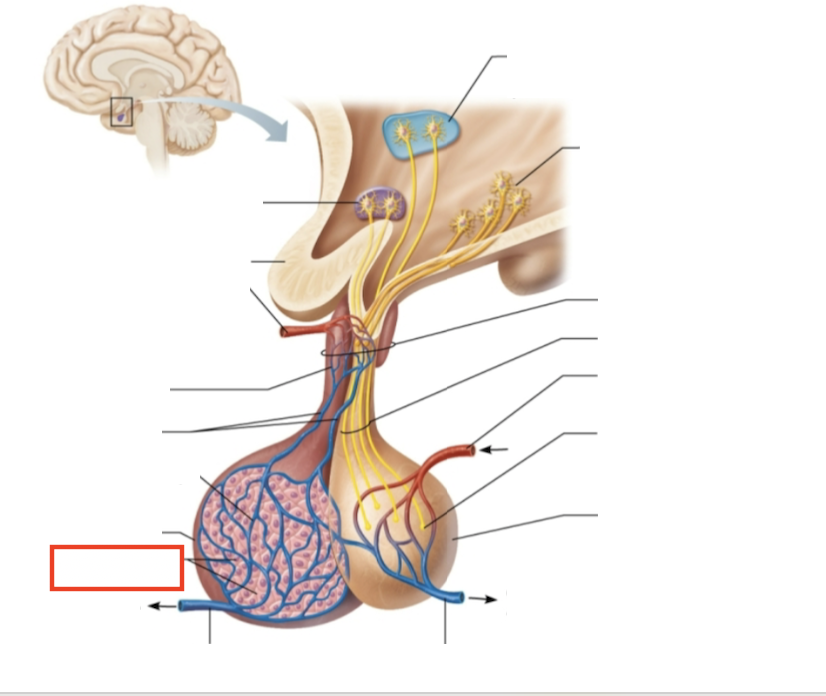

What structure is highlighted?

testes (male)

What are the target organs and effects of testosterone?

most cells of the body; promotes the maturation of the male reproductive organs, the development of secondary sex characteristics, sperm production, and sex drive

What hormone is produced by the testes?

testosterone

What stimulates testosterone production?

LH and FSH